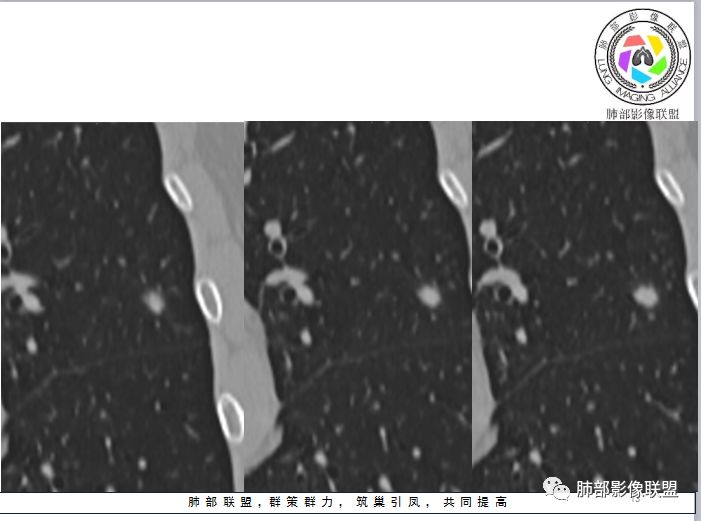

1、与炎性假瘤、恶性肿瘤鉴别:恶性肿瘤边缘膨隆,收缩也是毛毛糙糙的,炎性假瘤收缩力较强,边缘凹陷的多。隐球菌孤立结节收缩力弱,膨胀力也弱,与胸膜关系多为糊墙,部分有间隙。右边两幅可以看到胸膜增厚,胸膜下脂肪间隙增宽。晕中长毛刺,边缘平直,血管走行自然,鉴别肺癌。

3、与淋巴结鉴别:淋巴结小于1cm,多位于胸膜下。结节周围不应该有晕,可以与血管相连,与胸膜有多条影相连

4、与曲霉鉴别:曲霉少见孤立性病灶,除非寄生性的。出现长毛刺和晕则往往见于免疫力下降病例。曲霉不强化。血管炎孤立的少,一般是多态多灶,周围长索条,一般是包膜样强化。